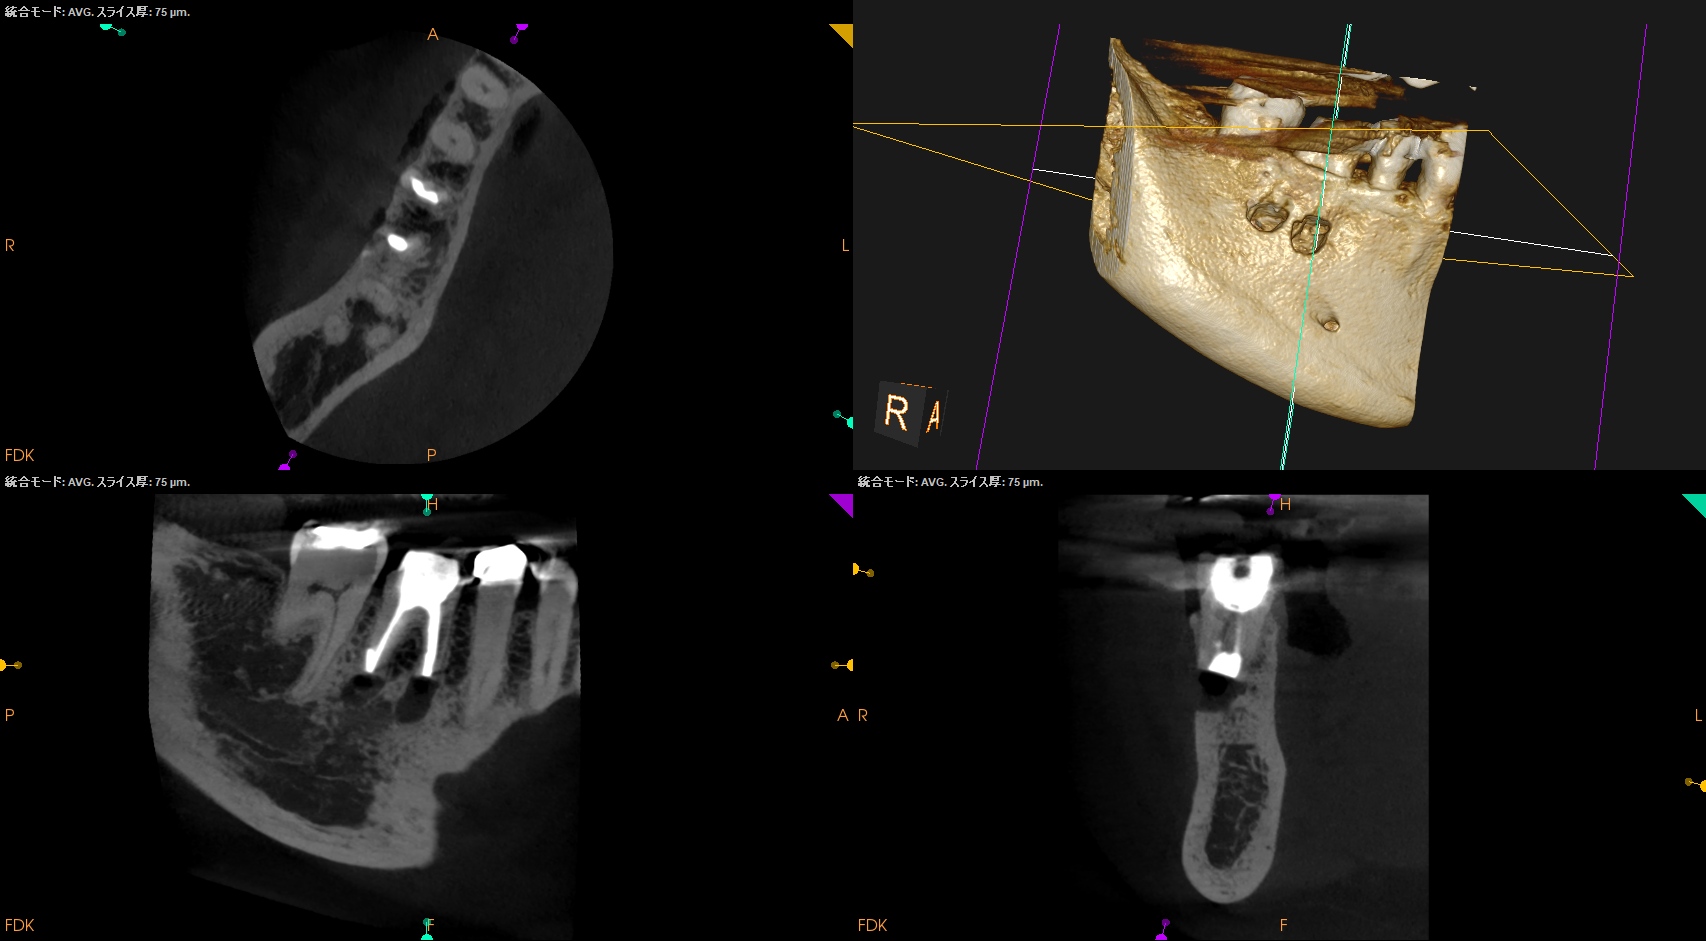

CBCT(2025.12.2)

MB

ML

D

M,Dの根尖部には病変がある。

またMもDも形成・根充が太くなされているので治療は成功率が低いであろう再根管治療ではなくApicoectomyだ。